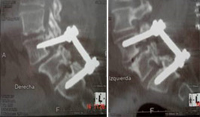

Izquierda: antes y después, espondilolistesis grado II tratada con implante percutáneo por el Dr. Morgenstern

Derecha: Implante percutáneo en canal estrecho